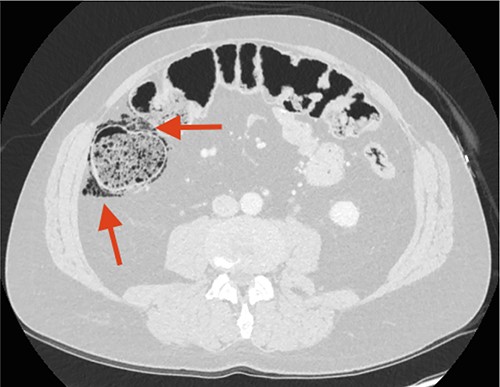

Three weeks later, a CT urography showed FIA, but the patient still had no symptoms indicative of peritonitis. Three months later, a CT scan showed progression of FIA and air bubbles in the wall of the ascending colon (Fig. 3).

CT scan performed 3 months after the first admission to the ED. The arrow points at increased FIA and air bubbles in the colonic wall as signs of Pneumatosis cystoides Intestinalis, PCI.

Pneumatosis cystoides intestinalis (PCI) was suspected.

Retrospectively, the two initial CT scans were reviewed with an independent radiologist, and gas-filled cysts were located in the wall of the ascending colon, representing PCI on both CT scans.